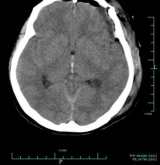

术后第一天复查颅脑CT

image.png